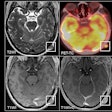

MR images show examples of visual R2* modifications within substantia nigra at baseline (24-72 hours after stroke) and at one-year follow-up in striatum (participants 1 and 2) and control groups (participants 3 and 4). Axial R2* maps are enlarged at mesencephalon level and one of the individual T2* echoes also is shown at follow-up. The substantia nigra is segmented in red ipsilateral to infarct and in green contralateral to infarct. Images without outlines are also shown. Brighter R2* spots are noted with red arrows. Asymmetry index of 95th percentile of R2* within substantia nigra (SN-AI95) measured in these participants is indicated for reference. Participants 1 and 2 show marked asymmetry of R2* within ipsilateral substantia nigra at follow-up, compared with baseline after infarct involving entire striatum (participant 1) or limited to putamen (participant 2). Asymmetry also is visible on individual T2* echo at follow-up. Conversely, no asymmetry was observed in participants 3 and 4 sparing striatum. Images courtesy of Radiology.Linck and colleagues also observed an association between high iron content and poor long-term physical outcomes for stroke patients, particularly when increased iron levels were found on the same side of the brain where the infarction occurred. For example, follow-up tests showed reduced performances of patients when they tried to use their nondominant arms and in a 10-mile walking test.